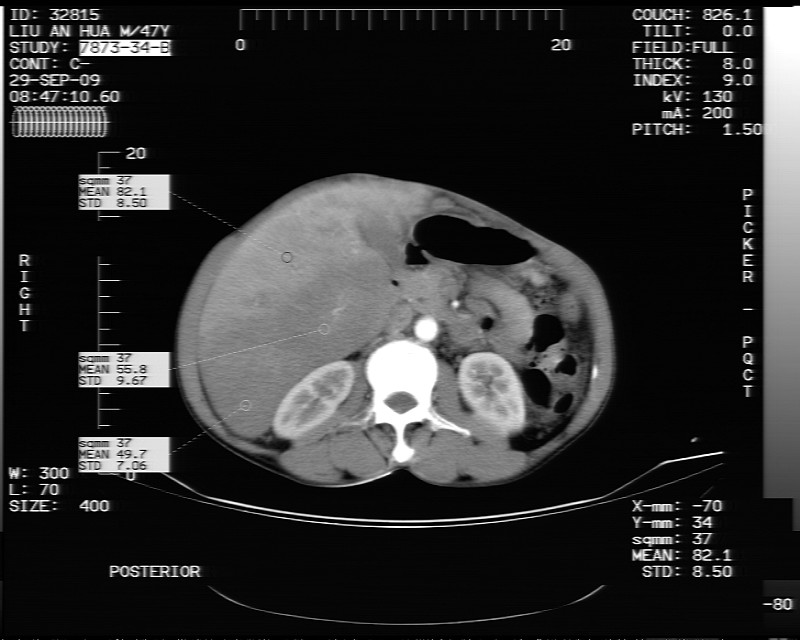

平扫示:

支持脂肪肝【无占位性,高低密度区同期强化,平扫与强化的密度成比例】

不均匀性脂肪肝。肝脏体积稍大,不除外合并肝功能损害。

1.脂肪肝;

2.右肾结石。

1、不均匀脂肪肝;2、布加氏综合症(肝脏肿大,门脉纤细,下腔海绵状变性,肠系膜上静脉显著扩张)。